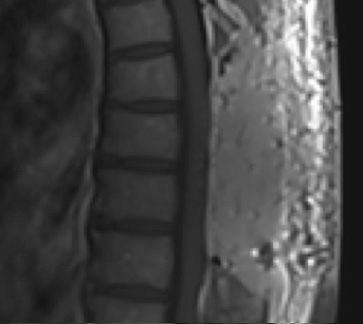

Postoperative MRI T1w demonstrating interval resection with cord re-expansion (blue arrow)

Postoperative MRI T1w demonstrating a gross total resection